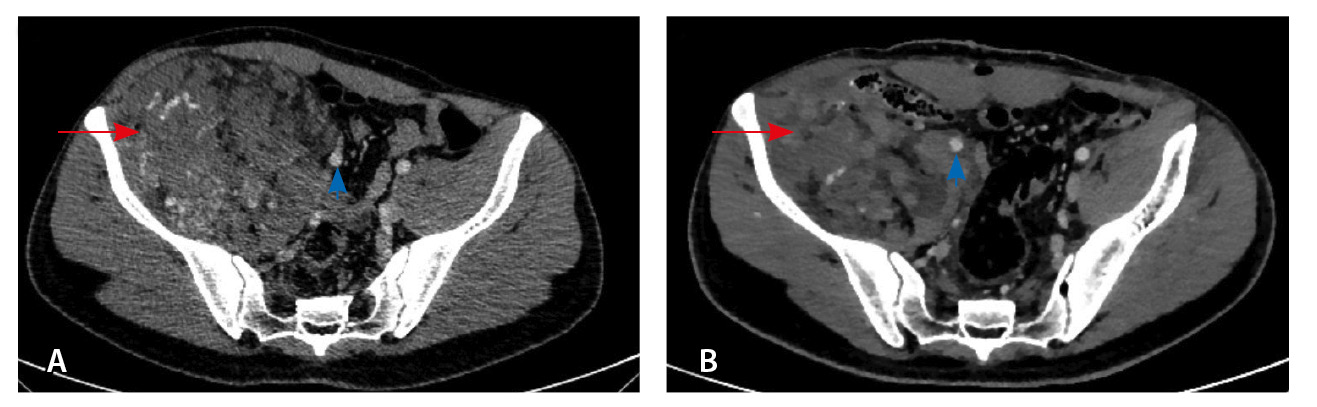

При контрольной томографии, проведенной на 5-е сутки после операции, забрюшинно справа определялась остаточная ткань опухоли размерами 125 × 81 × 90 мм. Резидуальный фрагмент прилегал к правой подвздошной кости, по ходу подвздошных сосудов, с распространением на переднюю поверхность правого бедра. Признаков экстравазации контрастного препарата не обнаружено (рис. 3).

Рис. 3. Мультиспиральная компьютерная томография органов брюшной полости и забрюшинного пространства с болюсным внутривенным контрастированием, венозная фаза. А – исследование до операции, Б – исследование после операции: резидуальный фрагмент образования (красная стрелка) тесно прилежит к подвздошной кости и подвздошным сосудам (головка синей стрелки)